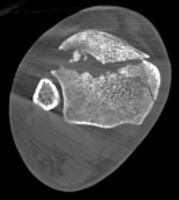

Pre-operative planning is the cornerstone of successful execution in complex pilon-variant tibial shaft fractures. The surgeon must transition from a conceptual understanding of the injury to a concrete, step-by-step surgical blueprint. This begins with high-quality orthogonal radiographs of the entire tibia, ankle, and knee. However, plain films drastically underestimate the degree of articular comminution and central impaction. A fine-cut computed tomography (CT) scan with 2D multiplanar reformats (coronal and sagittal) and 3D surface rendering is absolutely mandatory.

The CT scan allows the surgeon to map the fracture lines, identify the primary articular fragments (Chaput, Volkmann, medial malleolus), and quantify the degree of central die-punch impaction. In an AO/OTA 43C3.3 fracture, where no articular fragment is in continuity with the diaphysis, the surgeon must plan the sequence of reduction. Typically, the fibula is addressed first to restore lateral column length and rotation, provided the fibular fracture is not located at the level of the syndesmosis where fixation might interfere with the lateral surgical approach to the tibia.

The first objective of the internal fixation phase is the anatomic reconstruction of the articular block. The joint capsule is incised to allow direct visualization of the plafond. A femoral distractor or a temporary external fixator spanning the joint can be utilized to gain joint space and visualize the central impacted fragments. Using a dental pick or a Freer elevator, the central die-punch fragments are carefully disimpacted and brought down flush with the talar dome.

Once the articular surface is visually and fluoroscopically reduced, the resultant metaphyseal void is densely packed with cancellous allograft, autograft, or synthetic bone substitute to prevent late subsidence. The major articular fragments (Chaput, Volkmann, and medial malleolus) are then reduced around the central reconstructed block using pointed reduction forceps. Provisional fixation is achieved with multiple 1.6mm or 2.0mm Kirschner wires. Independent 3.5mm or 4.0mm lag screws can be placed outside the planned footprint of the definitive plate to secure the articular block.